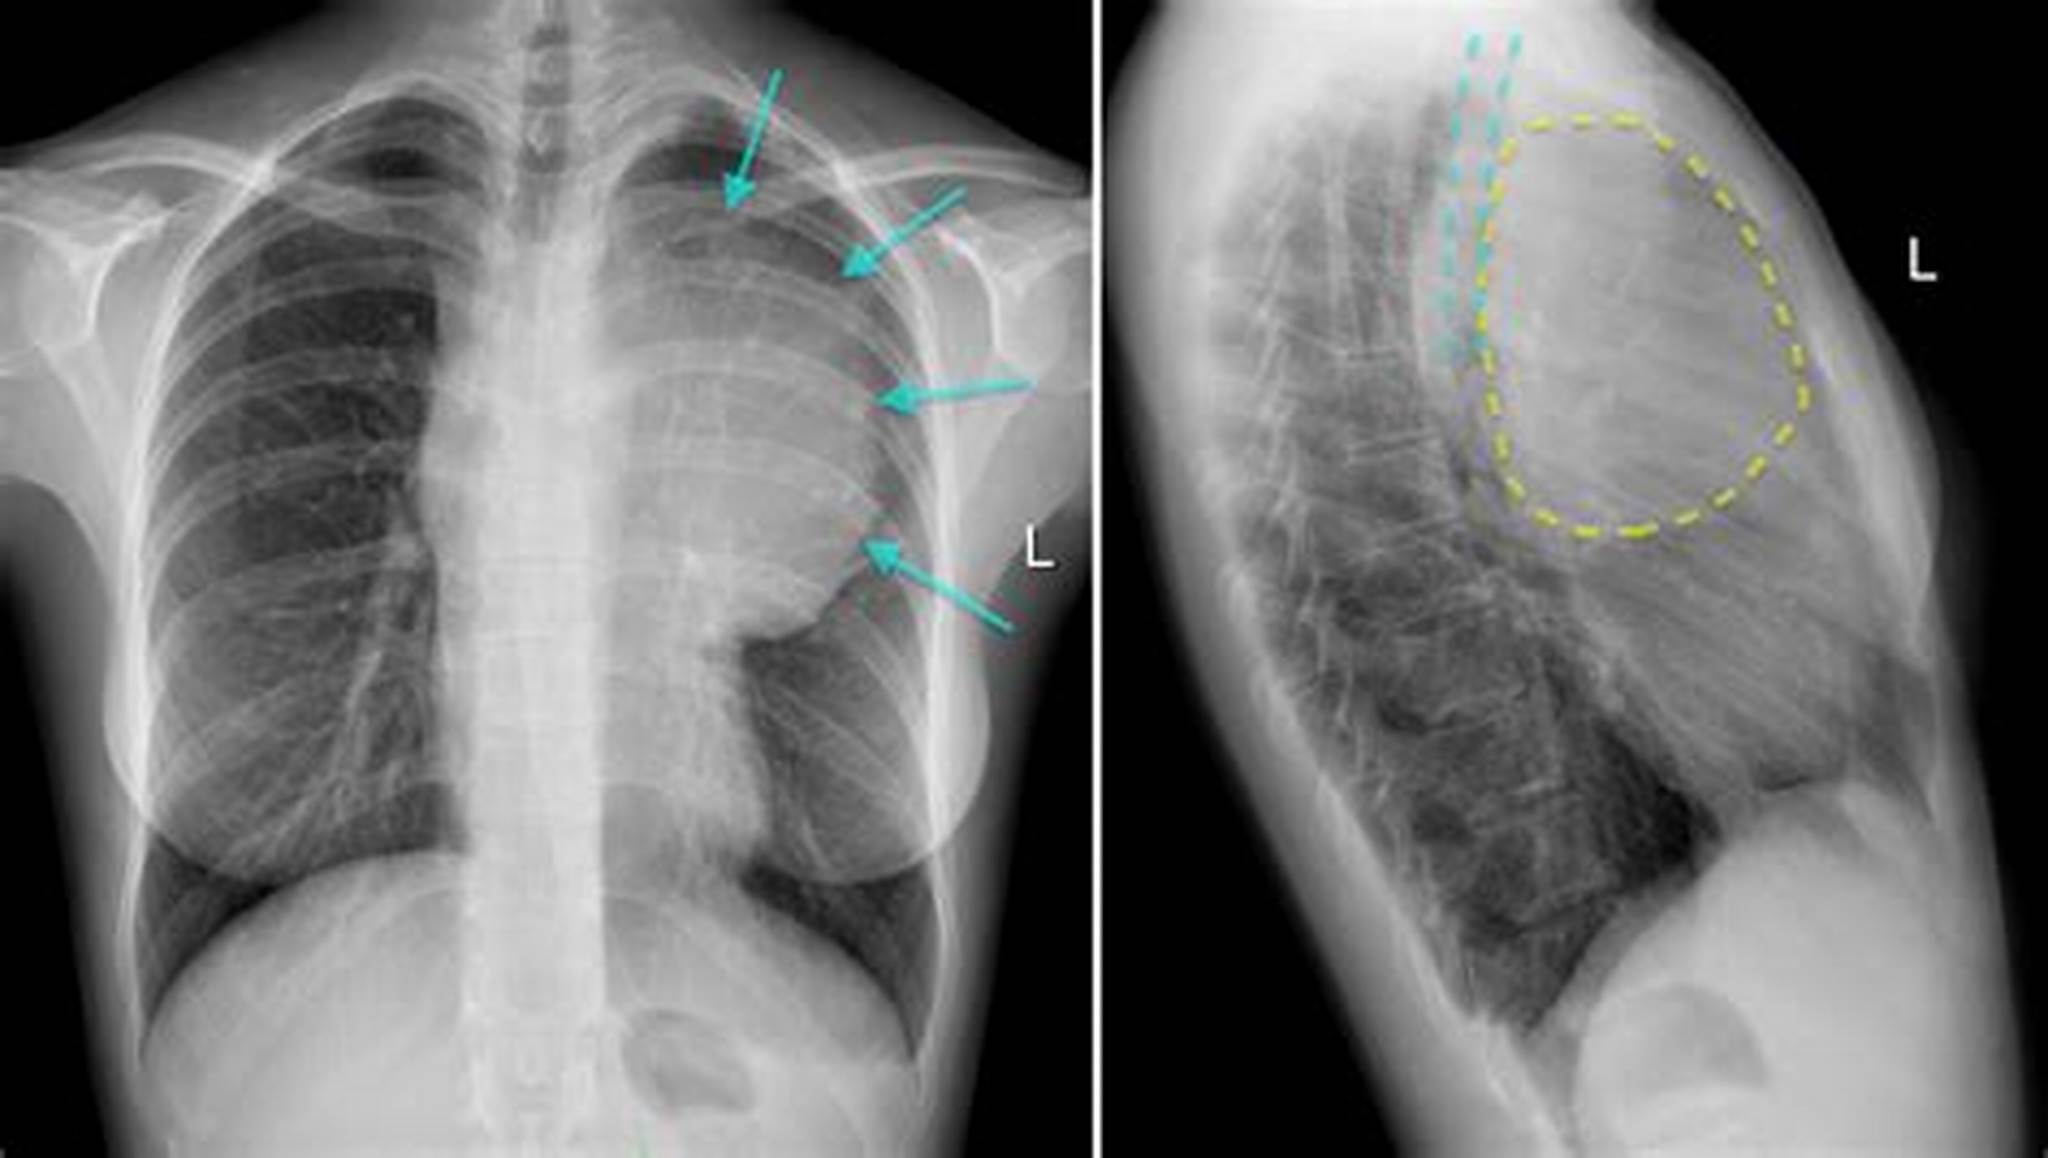

图1 胸部x线片 答案: 胸片(如图2)显示前纵隔肿块与

前上纵隔增宽高手来看看